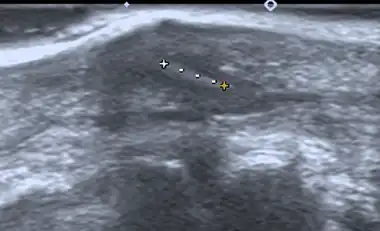

| Diagnostic method | Ultrasonography |

Imaging

If manual detection and localization fail, the main methods for medical imaging of splinters are:

- Medical ultrasonography – used to locate glass, metal, pencil graphite, some plastics, stone, and some types of wood.[6]

Small wooden splinters (1–4 mm) distant from bones are most easily detected by ultrasonography, while CT scan and magnetic resonance imaging have higher sensitivity for those near bones.[7]